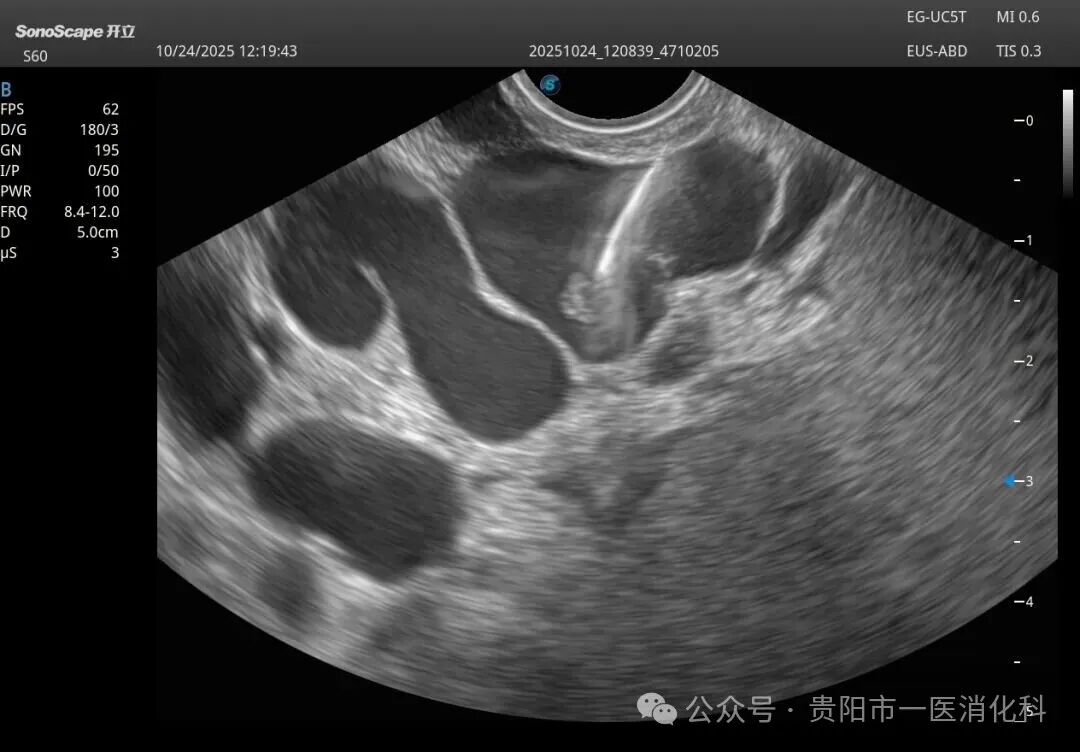

在王俊雄教授的全程指导下,手术如期进行。术中,专家团队首先将超声内镜送达胃底,屏幕上立即清晰显示出曲张静脉的横断面、深度、血流以及其来源血管。在超声的“火眼金睛”引导下,穿刺针犹如被安装了“GPS导航”,精准刺入目标血管。随后,医生们先将数个微弹簧圈送入血管内,构建一个坚实的“巢”,再注入医用组织胶水。弹簧圈与组织胶迅速结合,形成稳固的复合栓塞物,彻底封堵了致命的曲张静脉。整个手术过程流畅,术后患者生命体征平稳,安返病房。

1.精准可视:超声内镜让医生拥有了“透视眼”,能清晰看到血管的立体结构,实现指哪打哪,极大提高了成功率。